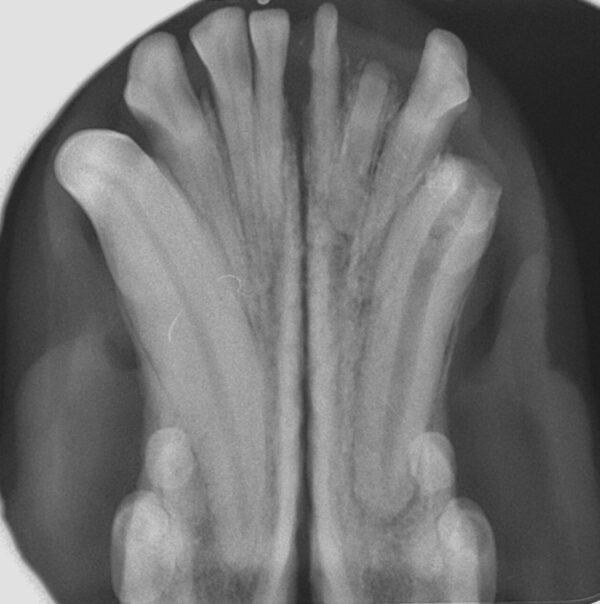

- Técnica paralela: el captador se coloca paralelo al diente y el haz de rayos X se proyecta perpendicular al mismo (imagen 3). Esta colocación solo puede llevarse a cabo con los dientes premolares y molares de la mandíbula.